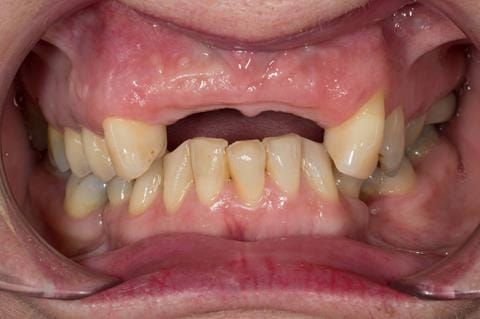

- High smile line showing gum above gingival zeniths of upper front teeth when smiling. Aesthetic failure of the upper four incisors with inflammation of the gingivae and mis-match of the gingival zenith levels.

- Other than the maxillary incisors the remaining dentition was in marginally better condition being moderately to heavily restored. Many will probably require replacement and restoration from time to time mainly from wear and tear owing to occlusal forces.

Following consultation and second discussion appointment the patient chose to have option 3 namely, a maxillary cobalt chromium based partial denture/protective occlusal splint. The clinical situation and treatment process is shown in detail below with photographs. The patient was successfully rehabilitated with this and her quality of life considerably improved. The clinical work was provided by Finlay and the technical work by Rowan.